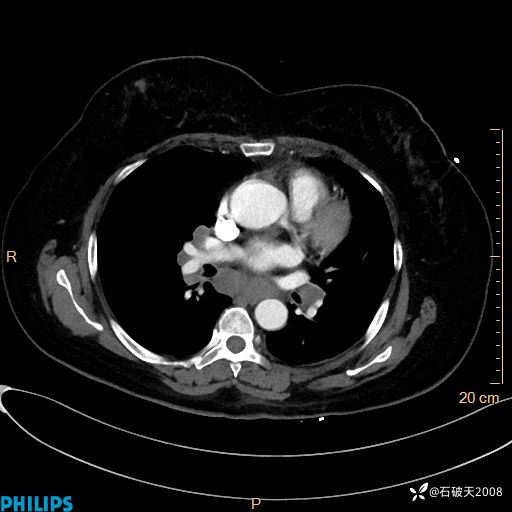

肺结节病?纵膈型肺癌?淋巴瘤?有点意思,欢迎围观

女 52岁 主 诉:咳嗽10余天,咳痰2天。

现病史:10余天前无明显诱因出现咳嗽,呈阵发性干咳,伴咽喉部发痒,无咽痛,无咳痰,无鼻塞、流涕、打喷嚏,无发热、畏寒、寒颤,无头痛、头晕,无胸闷、胸痛,无反酸、烧心,无腹痛、腹泻,无尿频、尿急,无皮疹等,在当地诊所求治,给予口服药物治疗(具体不详),病情无好转。遂在当地社区卫生服务中心开具口服药物治疗(具体不详),疗效欠佳。2天前出现咳痰,在我院门诊求治,行胸部CT提示肺部感染,建议住院,患者要求口服药物治疗,目前仍咳嗽、咳白色粘痰,白天量多,夜间自觉喉部喘鸣音,遂再次来院就诊,以“肺部感染”为诊断收入院。发病以来,神志清,精神可,饮食可,夜间睡眠差,大小便正常,近期体重无明显变化。

肺窗

纵隔窗

动脉期

静脉期